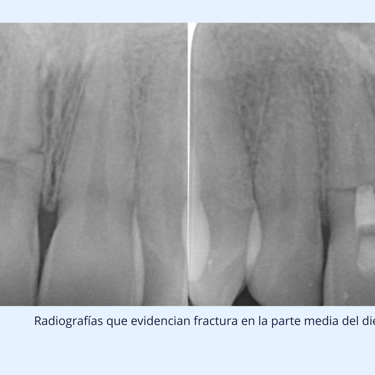

Las fracturas en la raíz del diente son más difíciles de detectar. El dentista puede usar radiografías y pruebas de presión para detectar el daño. En algunos casos, una fractura radicular puede no ser visible, y el diente puede requerir extracción.

Radiografías:

Radiografía Periapical: Ayuda a visualizar la raíz del diente y detectar cualquier fractura.